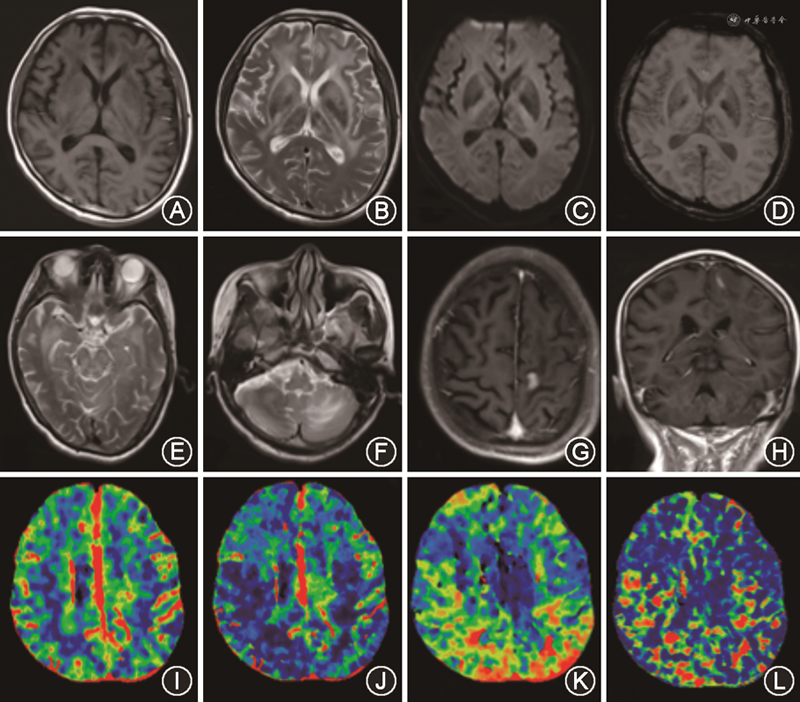

3.头颅影像学特点:病例1的头颅磁共振成像显示双额颞叶白质、脑干、小脑弥漫性病变,局部片状强化。头颅灌注CT提示头CT脑动脉(CTA)及CT脑静脉(CTV)未见明显异常,双侧小脑、双侧额顶枕叶低灌注(图1)。病例2的头颅磁共振成像显示大脑白质多发斑片状病灶,边界不清(图2)。